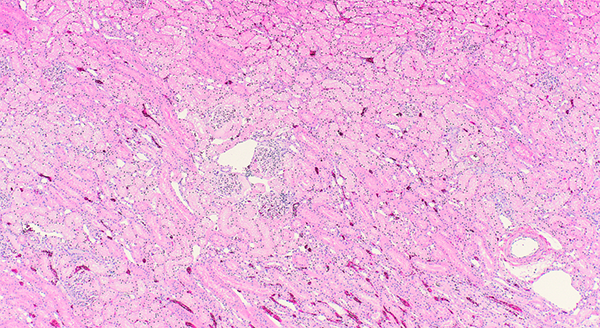

Routine staining with hematoxylin and eosin (H&E) involves immersing slides in a series of reagents over approximately two hours, producing the characteristic purple-and-pink appearance that allows the pathologists to evaluate tissue architecture and detect abnormalities. The stained slides are then coverslipped with mounting medium to preserve the tissue and stain. In addition to routine H&E staining, the Histology section performs a range of special stains that help pathologists identify fungi, bacteria, minerals and other microscopic components.

Histology plays a critical role in identifying cellular changes associated with diseases such as cancer, infections, and inflammation, and it remains the gold standard for cancer diagnosis. Critically, the diagnostic quality of histopathology begins the moment the tissue is collected. Proper sampling, prompt fixation, and accurate documentation of the collection site and clinical history are essential for obtaining meaningful diagnostic information.